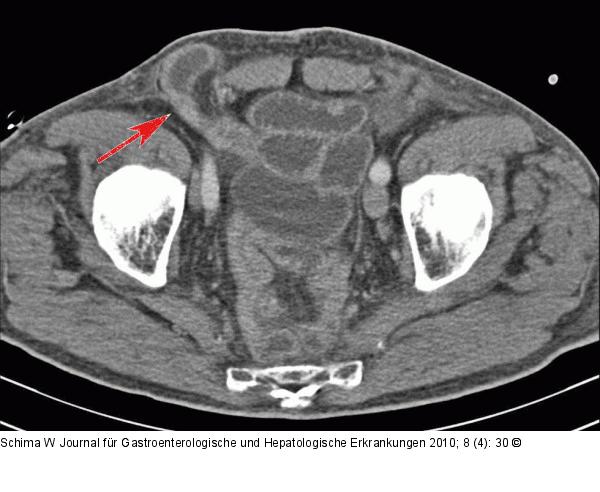

Abbildung 1b: Dünndarmschlinge Durchtritt einer komprimierten Dünndarmschlinge durch den Leistenkanal (Pfeil). |

Durchtritt einer komprimierten Dünndarmschlinge durch den Leistenkanal (Pfeil). |